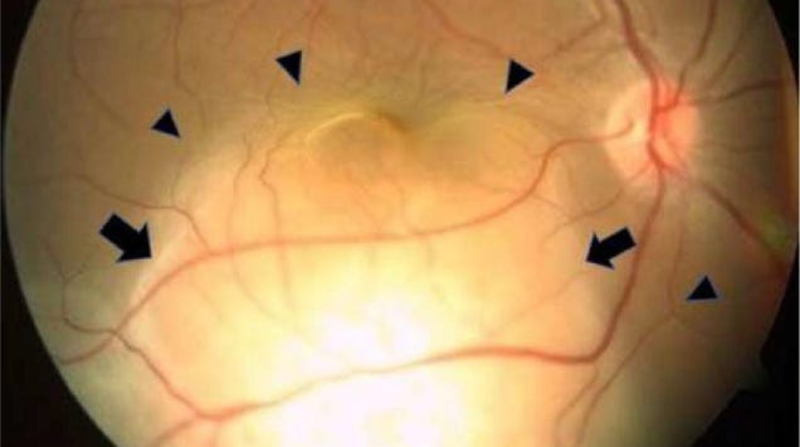

A woman’s blindness in her right eye turned out to have an unexpected and frightening cause: metastatic lung cancer. Doctors in India reported the strange occurrence last month—seemingly the first of its kind ever documented.